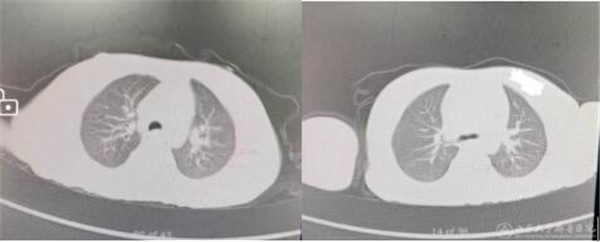

由于患儿服用百草枯量比较大,初期的治疗并不顺利。积极全面的治疗方案仍难以阻挡病情的进展,口周及口腔黏膜溃疡的疼痛令患儿无法进水进食,咽喉部的损伤加之气道分泌物的增多导致声音嘶哑,肺部进行性加重的病变呈现出愈加明显的呼吸困难和间断发热。在其父母濒临绝望之时,刘心洁主任反复耐心的向其讲解病情、鼓励家长,始终坚持治疗、加强护理。滴水不进,及时加用静脉营养以维持能量需要;呼吸不畅,予以加强呼吸道治疗和管理;药物浓度过高,给予充分的血液净化治疗。入院第3天,复测的尿百草枯浓度已由入院时的>100μg/ml迅速降至3μg/ml;经过儿童重症团队连续5天进行血液净化治疗,入院第7天,血清中的百草枯浓度已降至低于检测下限;入院第11天,患儿可自主进食,体温恢复正常;入院第13天,患儿声嘶明显减轻、口腔溃疡较前好转。8月4日,入院后第5次检查胸部CT,仅提示“右肺下叶背段模糊影,考虑渗出性改变”,此时距离患儿入院已21天,患儿无明显呼吸困难,能够正常进食和活动,各重要脏器功能的相关指标也几近正常。

(患儿胸部CT入院初及出院前)